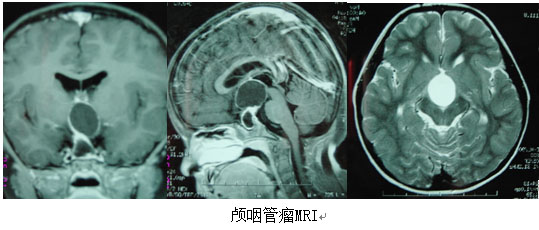

顱咽管瘤是指發(fā)生于顱咽管殘余上皮細(xì)胞的腫瘤,是常見(jiàn)的先天性腫瘤,約占60%,占顱內(nèi)腫瘤的5%—6%。為良性腫瘤,可見(jiàn)任何年齡,以兒童及青年多見(jiàn),男女比例約為2:1。臨床表現(xiàn)主要為頭痛、嘔吐、視力減退、視野缺損及視神經(jīng)萎縮;發(fā)育遲緩,性功能障礙,女性月經(jīng)不調(diào)、閉經(jīng)、不孕,男性性欲減退、陽(yáng)萎;體溫調(diào)節(jié)失常、多飲、多尿、消瘦、精神異常;向鄰近生長(zhǎng)者可有偏癱、感覺(jué)減退等相應(yīng)壓迫癥狀、體征。手術(shù)治療為首選,年齡越小,越易全切,并發(fā)癥越少,故早診早治是關(guān)鍵。

顱咽管瘤起源于垂體胚胎發(fā)生過(guò)程中殘存的扁平上皮細(xì)胞,是一種常見(jiàn)的先天性顱內(nèi)良性腫瘤,大多位于蝶鞍之上,少數(shù)在鞍內(nèi)。顱咽管...【詳細(xì)】